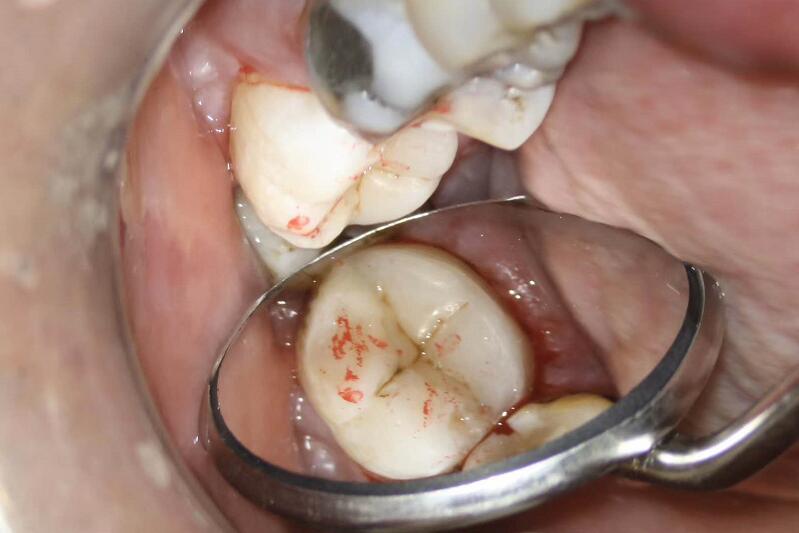

显微根管一次治疗术 +显微仿生修复术,一次性解决困扰袁师傅多年的牙疼和吃饭问题!感谢袁师傅的配合,他说:其实在享受这个过程!极致微创、文鸣仿生,让更多人不把牙齿磨小做牙套,在路上!……